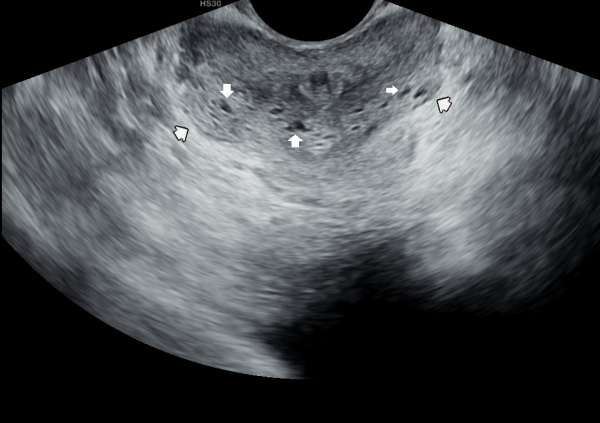

주2회 전립선의 표적 치료후 고환의 미석증이 줄어 들고 있는 경직장 전립선 초음파 검사 사진

Transrectal ultrasound image showing a reduction in testicular microlithiasis after twice-weekly targeted prostate treatment.